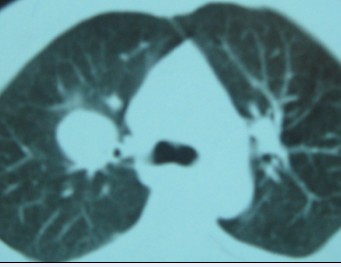

右肺上叶良性肿瘤---错构瘤/硬化性血管瘤/炎性假瘤等。

右肺上叶良性肿瘤---错构瘤/硬化性血管瘤/炎性假瘤等。支持!

支持 右肺上叶良性肿瘤---错构瘤/硬化性血管瘤/炎性假瘤等。

右肺上叶良性新生物---炎性假瘤或结核球/错构瘤/硬化性血管瘤等